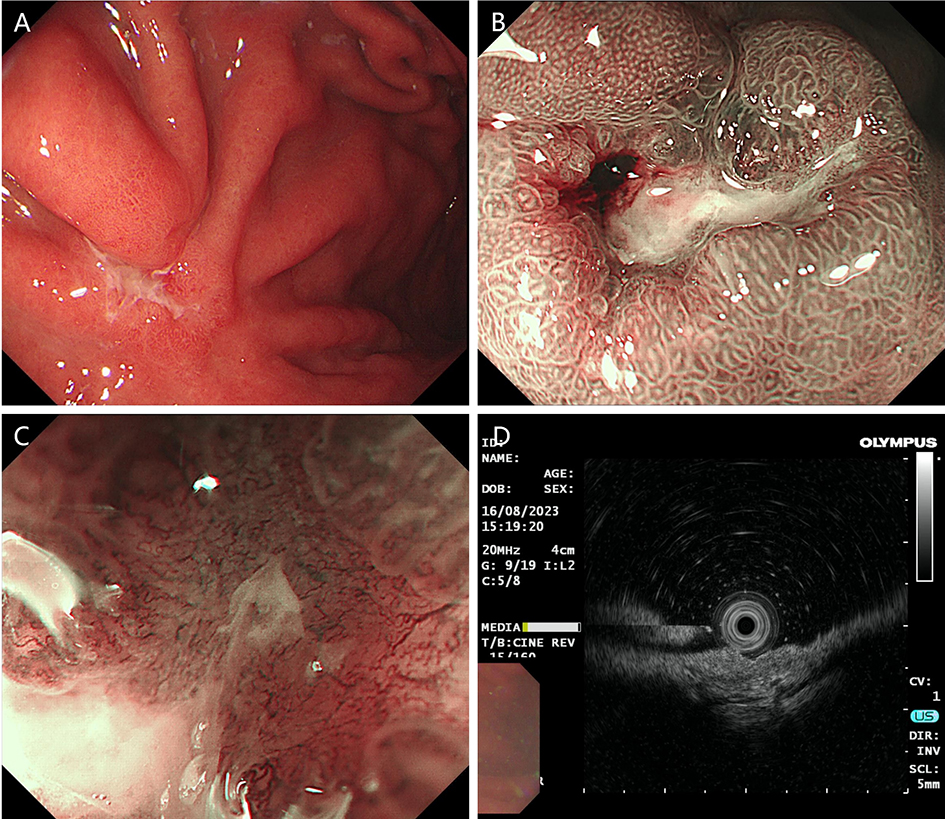

1. Classic digestive tube channel. The classic digestive tube approach refers to the path through the continuous tube from the mouth to the anus. The wall of the tube is generally divided into the mucosal layer, submucosal layer, muscularis propria layer and serous layer, from the intracavitary to the extracavitary layer. So far, most gastrointestinal endoscopy operations have carried out in this tube.

After endoscopic resection of circumferential esophageal lesions, almost 100% of patients experienced symptoms like esophageal stenosis and an inability to eat. Our team is the first in the world to carry out endoscopic autologous skin flap transplantation to prevent stenosis after endoscopic resection of esophageal circumferential lesions (figure 2.1), and 19 cases of autologous transplantation of skin flaps and simple placement of an esophageal stent for the prevention of esophageal stenosis were compared. The results showed that rate of stent removal for the group who had received an autologous skin flap transplantation was significantly reduced compared to the group with a simple esophageal stent (36.8%–78.9%). Currently, this research is also aimed at optimizing surgical and transplant methods, so as to improve the survival rate of skin flaps and to reduce the rate of occurrence of esophageal stenosis.